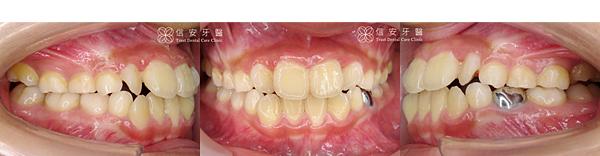

▋ 矯正前:

▲案例A小弟牙齒凌亂、齒列擁擠,側面看略有暴牙問題。

▲牙骨與牙齒關係不協調導致空間不足。